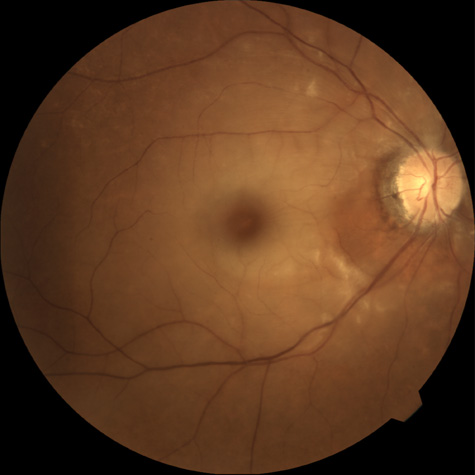

When a branch retinal artery is obstructed, there is usually whitening of the retina in the area supplied by the artery (Fig. 2). In most eyes (62% in one series), emboli are responsible for the obstruction.94 The temporal branch arteries are involved in almost all cases that have been reported,92,94 but whether this is because nasal branch retinal artery obstructions are rare or because such obstructions are simply asymptomatic is unknown. The characteristics of a branch retinal artery obstruction on intravenous fluorescein angiography are similar to those for central retinal artery obstruction.

Fig. 2. Multiple branch retinal artery obstructions in a young woman with encephalopathy and hearing loss. (Photograph courtesy of Jack W. Pierce, M.D.)

The patient describes either a sudden loss of vision if the branch retinal artery involves the macula or a visual field defect or both. Initial visual acuities can range from 20/15 to hand movements, but in one series, more than three-fourths of all patients had an initial visual acuity of 20/40 or better.94 Most patients who are seen with have branch retinal artery obstruction have unilateral obstructions, but about 8% later develop branch retinal artery obstruction in the opposite eye.94

Occasionally, patients present with a bilateral branch retinal artery obstruction.94 Some have obstructive retinal arteries without evidence of systemic abnormalities,95,96 whereas others have accompanying symptoms such as deafness.97,98 Some younger patients—usually women—have been reported to have an idiopathic syndrome of branch retinal artery obstruction, encephalopathy, and hearing loss (Susac syndrome).99–104,406 The eyes on these patients are characterized by significant systemic thromboembolic events; recurrent bilateral retinal arterial occlusions; segmental arteriolar staining by fluorescein angiography, occasionally associated with periarteriolar retinal whitening or mild vitreous cells; and a predilection for vestibuloauditory or transient sensorimotor symptoms.104 Some patients, however, present with only recurrent bilateral retinal arteriolar occlusions and never develop the associated vestibuloauditory or sensorimotor systems; whether these patients have a partial manifestation of Susac syndrome is unknown. The etiology of branch retinal artery obstruction in most cases is similar to that of central retinal artery obstruction (see Table 1). Retinal diseases (such as toxoplasmosis) can also cause branch retinal artery obstruction.